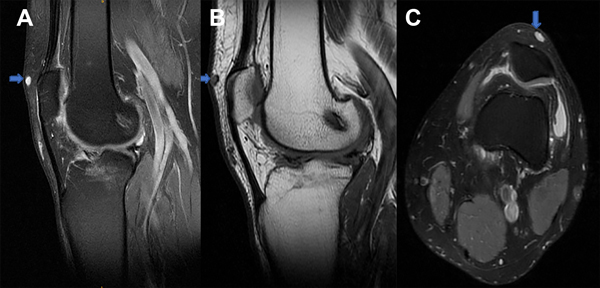

En la resonancia magnética se evidencia reconstrucción de ligamento cruzado anterior, lesión meniscal interna y una masa hipointensa en secuencias ponderadas en T1 y una masa hiperintensa en las ponderadas en T2, en región suprapatelar externa (fig. 2).

Figura 2: Resonancia magnética de rodilla izquierda. A) Imagen hiperintensa en T2 en corte sagital. B) Imagen hipointensa en T1 en corte sagital. C) Imagen hiperintensa en T2 en corte axial.